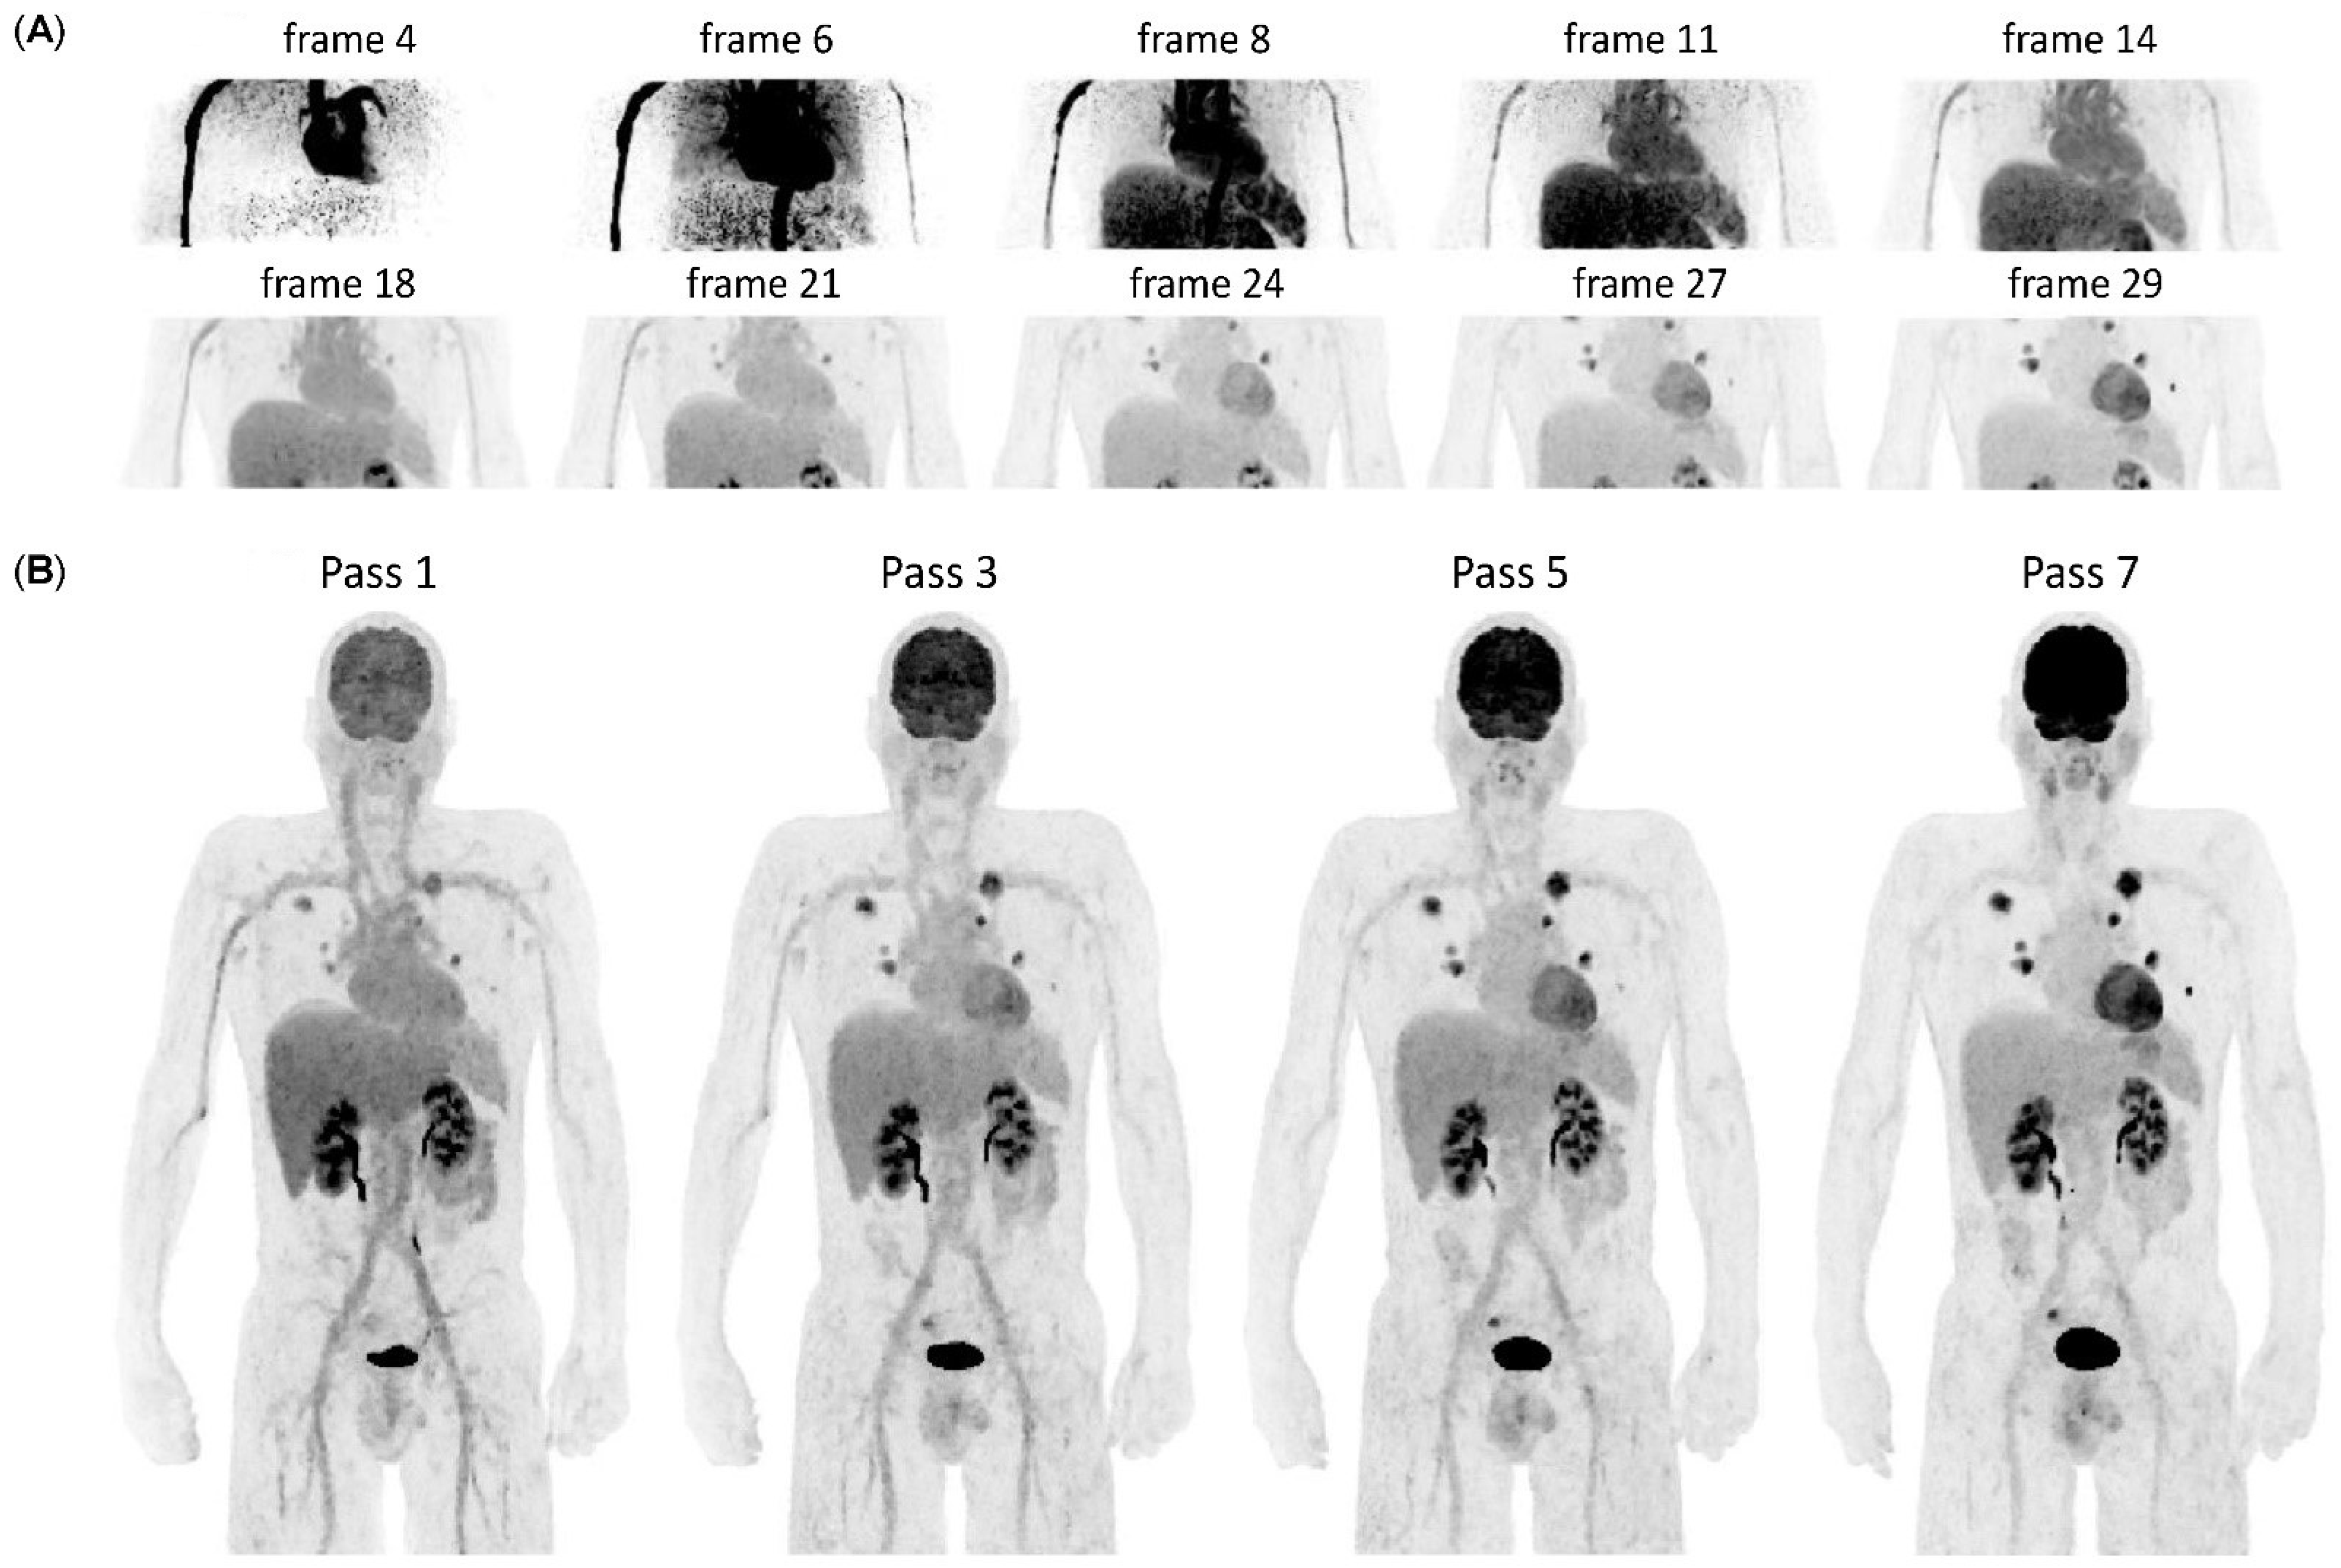

2.2. WBD PET Acquisition and Image Reconstruction

2.3. Generation of Patlak Parametric Images